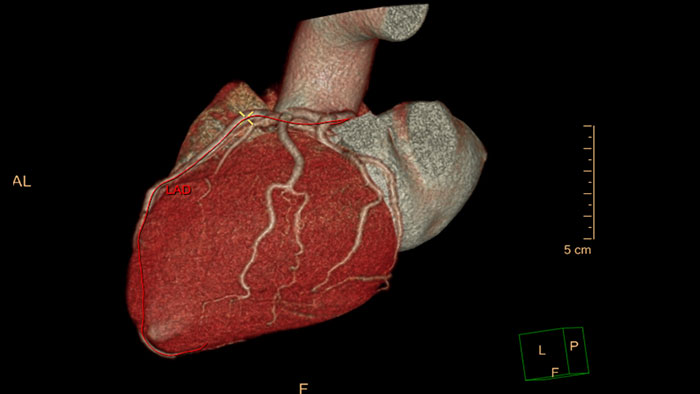

One-click 3D calcium segmentation

One-click 3D segmentation and quantification for coronary arteries calcifications including mass, Agatston, and volume scores.

Comprehensive cardiac analysis

Designed to assist the user in viewing, analyzing and quantifying dedicated Cardiac CT Angiograms, mainly for coronary arteries analysis on Coronaries CT Angiogram (CCTA) data.